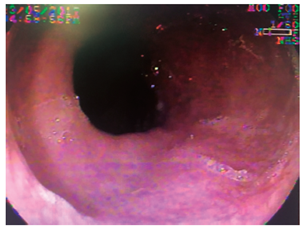

Varón de 76 años, que fue remitido por consultar por dolor intenso en el hipocondrio derecho, de tres días de evolución, malestar general, astenia y adinamia. Al examen estaba adolorido, taquicárdico, taquipneico, afebril, ictérico, con tirajes intercostales, estertores en base derecha y signo de Murphy positivo. Antecedente de diabetes mellitus tipo 2 e hipertensión arterial. Con diagnósticos de neumonía basal derecha, septicemia, trombocitopenia, hipertrofia prostática benigna, insuficiencia renal crónica agudizada, colelitiasis con dilatación de la vía biliar y colédocolitiasis. Durante la ultrasonografía endoscópica, como hallazgo incidental se describe mucosa esofágica negra en su totalidad, recubierta de exudado mucoso, sin erosiones, úlceras ni estrechez, con mucosa por debajo de la línea Z de aspecto usual. La videoendoscopia demuestra ulceración esofágica desde los 21 cm de la arcada dentaria, que se torna circunferencial a los 23 cm, recubierta por fibrina, aspecto negro y grisáceo desde los 27 cm hasta la unión cardioesofágica (Figuras 5, 6 y 7), respetando la mucosa cardial (Figura 8). La colangiopancreatografía retrógrada endoscópica (CPRE) demuestra vía biliar extrahepática dilatada con defecto de llenado en el tercio medio y distal; se practica esfinterotomía pequeña (por trombocitopenia de 31 000 x mm3) (Figura 9) y se extraen cálculos pequeños con balón, dejando un stent plástico de 7 Fr x 7 cm, con drenaje de bilis clara con microcálculos. El paciente evoluciona satisfactoriamente y sale del hospital con resolución del cuadro doloroso e ictérico. A las 10 semanas se encuentra asintomático, sin aceptar la realización de procedimientos de control.

Los hallazgos endoscópicos son diversos y requieren que se descarten otras etiologías que producen alteraciones similares, como la ingestión de cáusticos, otros tóxicos o carbón, infecciones, radioterapia o melanoma metastásico, entre otros 3,10. Los hallazgos pueden ir desde membranas blanquecinas, que al removerlas dejan una mucosa grisácea o negruzca, hasta necrosis difusa con exudados amarillentos adherentes, ulceración en la mayoría y aspecto negruzco o grisáceo, demarcado por la unión gastroesofágica, con región cardial de aspecto usual, como se describen en nuestros casos. El espectro de lesiones asociadas es amplio, como hemorragia gástrica o duodenal, ulceraciones y perforaciones, representadas en la casuística general con úlceras duodenales (10; 4 %), gástricas (2; 1 %), necrosis isquémica duodenal (2; 1%); sangrado activo (4; 2 %), perforación esofágica (3; 1,3 %) y duodenal (1; 0,5 %) (Tabla 1).